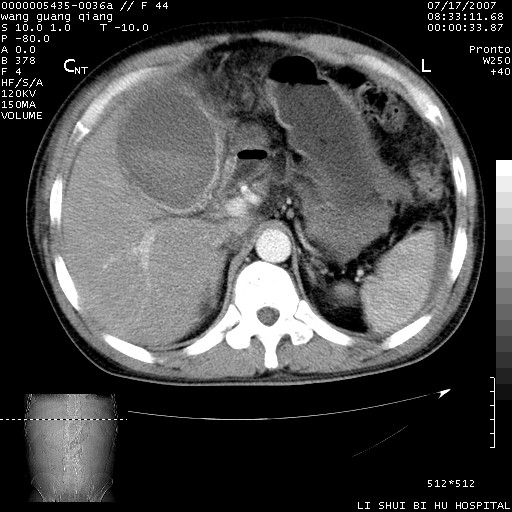

以下是引用dyqct在2007-7-18 10:46:00的发言:[br]胆囊明显增大,壁增厚,明显强化;后下方见大片高密度区,ct值68hu,无强化,周围见多数条纹状高密度影,边界不清。双膈下间隙、肝肾隐窝见带状及片状低密度区。[br]右侧胸壁后缘亦见新月形水样密度区。[br]考虑:1、急性胆囊炎伴周围出血;[br] 2、少量腹水、右侧少量胸腔积液。[br][br][本贴已被 dyqct 于 2007-7-18 10:48:47 修改过]